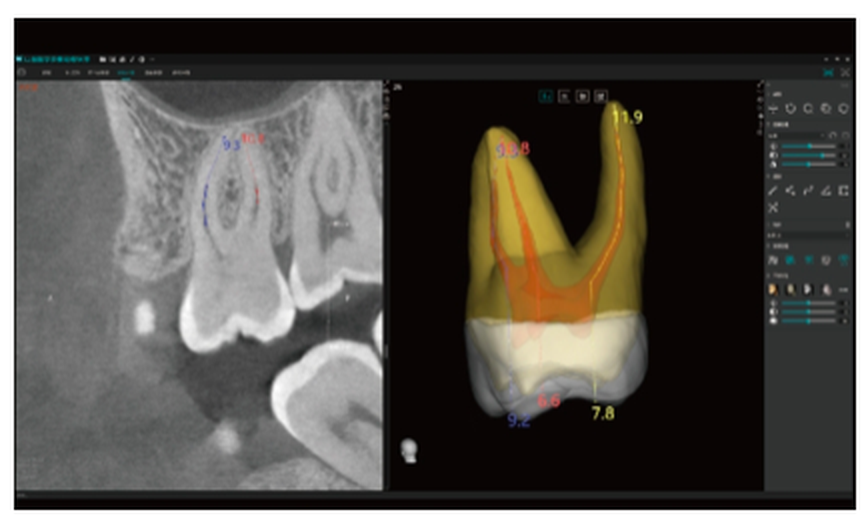

Inclui o Módulo Endo Easy*

Análise Dentária 3D Abrangente: segmentação completa do dente com medições automáticas, planeamento do percurso de acesso e avaliação precisa de cáries.

Visualização Endodôntica Avançada: observação 3D de cáries interproximais, defeitos estruturais e morfologia dos canais radiculares, garantindo que nenhum canal passa despercebido.

Segmentação Completa da Estrutura Dentária: realce automático do esmalte, dentina, polpa e estruturas periodontais, permitindo a visualização das alterações morfológicas.

Mapeamento Avançado dos Canais Radiculares: visualização clara dos canais MB2 e em forma de C, apoiando um tratamento endodôntico preciso e minimizando o risco de canais não detetados.

Medição Automática do Canal Radicular

Medição do Canal Radicular: precisa, automática e fiável — evita erros manuais e permite o planeamento pré-operatório.

Planeamento Endodôntico Inteligente: mede com precisão o comprimento do canal radicular, garantindo um tratamento previsível e eficiente.

Visualização Especial dos Canais Radiculares

vermite a visualização de morfologias especiais dos canais radiculares (MB2 e canais em forma de C), orientando os procedimentos endodônticos.

Ajuda a evitar a omissão de canais.